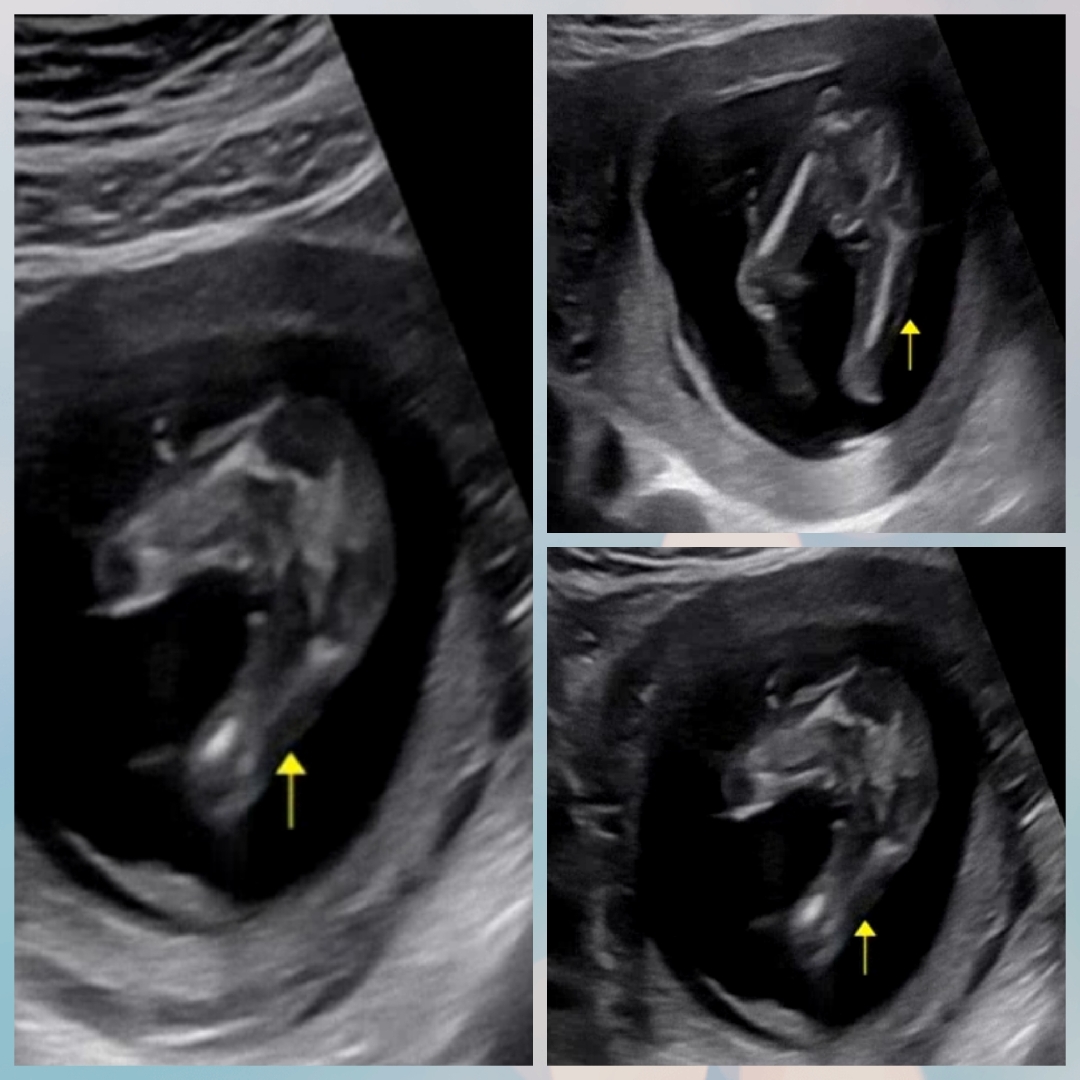

15주 초음파에용 성별ㅠㅠ

15주인데 세컨병원이라 그런지 성별모르신다고하네욤... 아무것도 안보이는거 같기도한데 두번째사진엔 뭔가보이는거 같고ㅠㅠ 저의 궁금증 풀어주실분 계실까요🙏